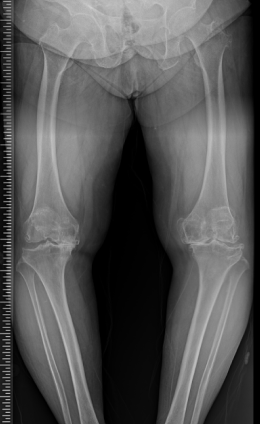

수술 전후 사례

-

수술 전

수술 후